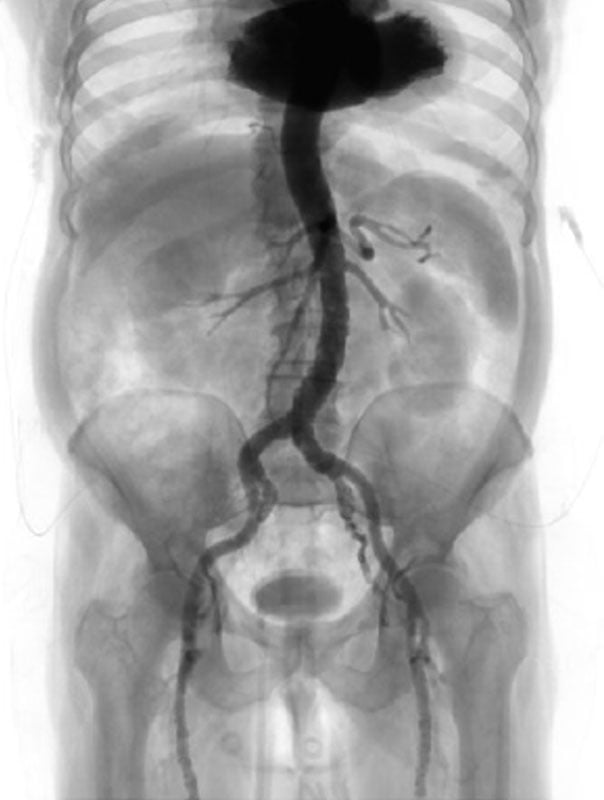

Case planning: CT

LAO 3° - cranial 19°

RAO 14° - caudal 9°